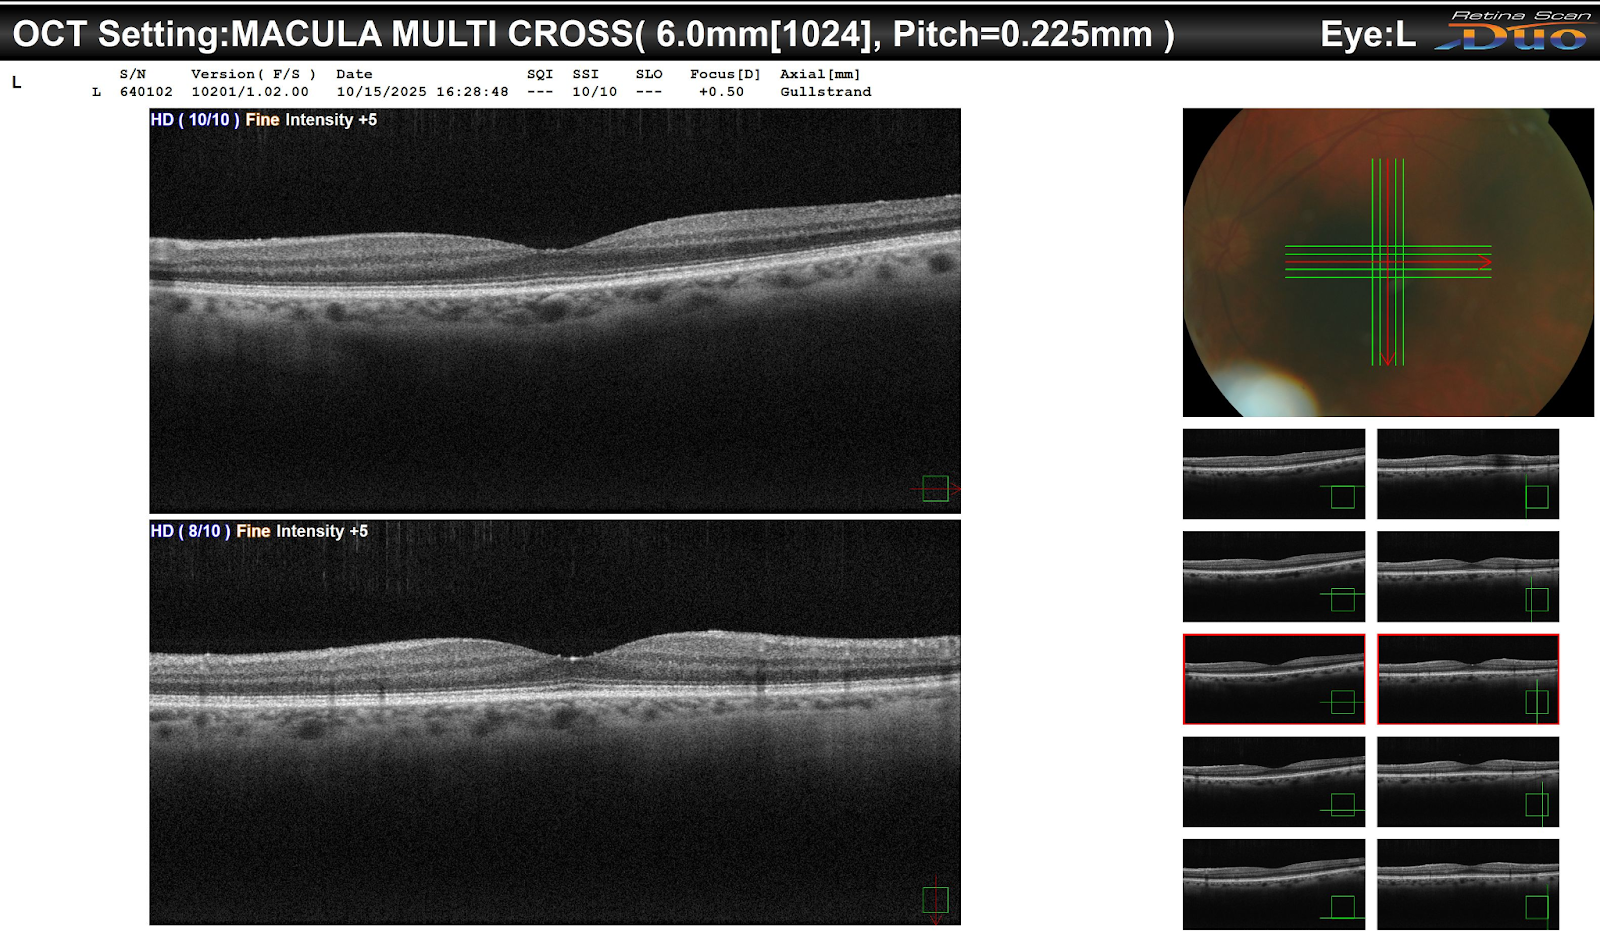

A 52-year-old patient was referred for evaluation due to optic nerve abnormalities noted during a routine exam. BCVA was 20/25 OD and 20/20 OS. IOPs were 18 mmHg OD and 16 mmHg OS. Anterior segment examination was unremarkable. Posterior segment evaluation revealed enlarged optic nerve cups and subtle nerve fiber layer thinning. Visual field testing showed early peripheral defects. OCT imaging confirmed structural changes consistent with optic nerve stress.

The reviewing retina specialist emphasized careful assessment of optic nerve morphology and correlated structural-functional analysis. High-quality OCT imaging is essential to detect early changes before significant visual field loss occurs. The importance of repeated, consistent IOP measurements and attention to family history was highlighted. Clinicians should maintain vigilance for subtle peripheral defects on visual field testing. Early identification supports timely specialist referral and patient counseling.

Optic nerve cupping can result from a range of chronic or acute stressors. OCT is a sensitive tool for detecting early thinning of the retinal nerve fiber layer and ganglion cell layer. Structural changes often precede functional loss, making early imaging crucial. Monitoring trends over time is essential to differentiate physiologic variations from pathologic progression.